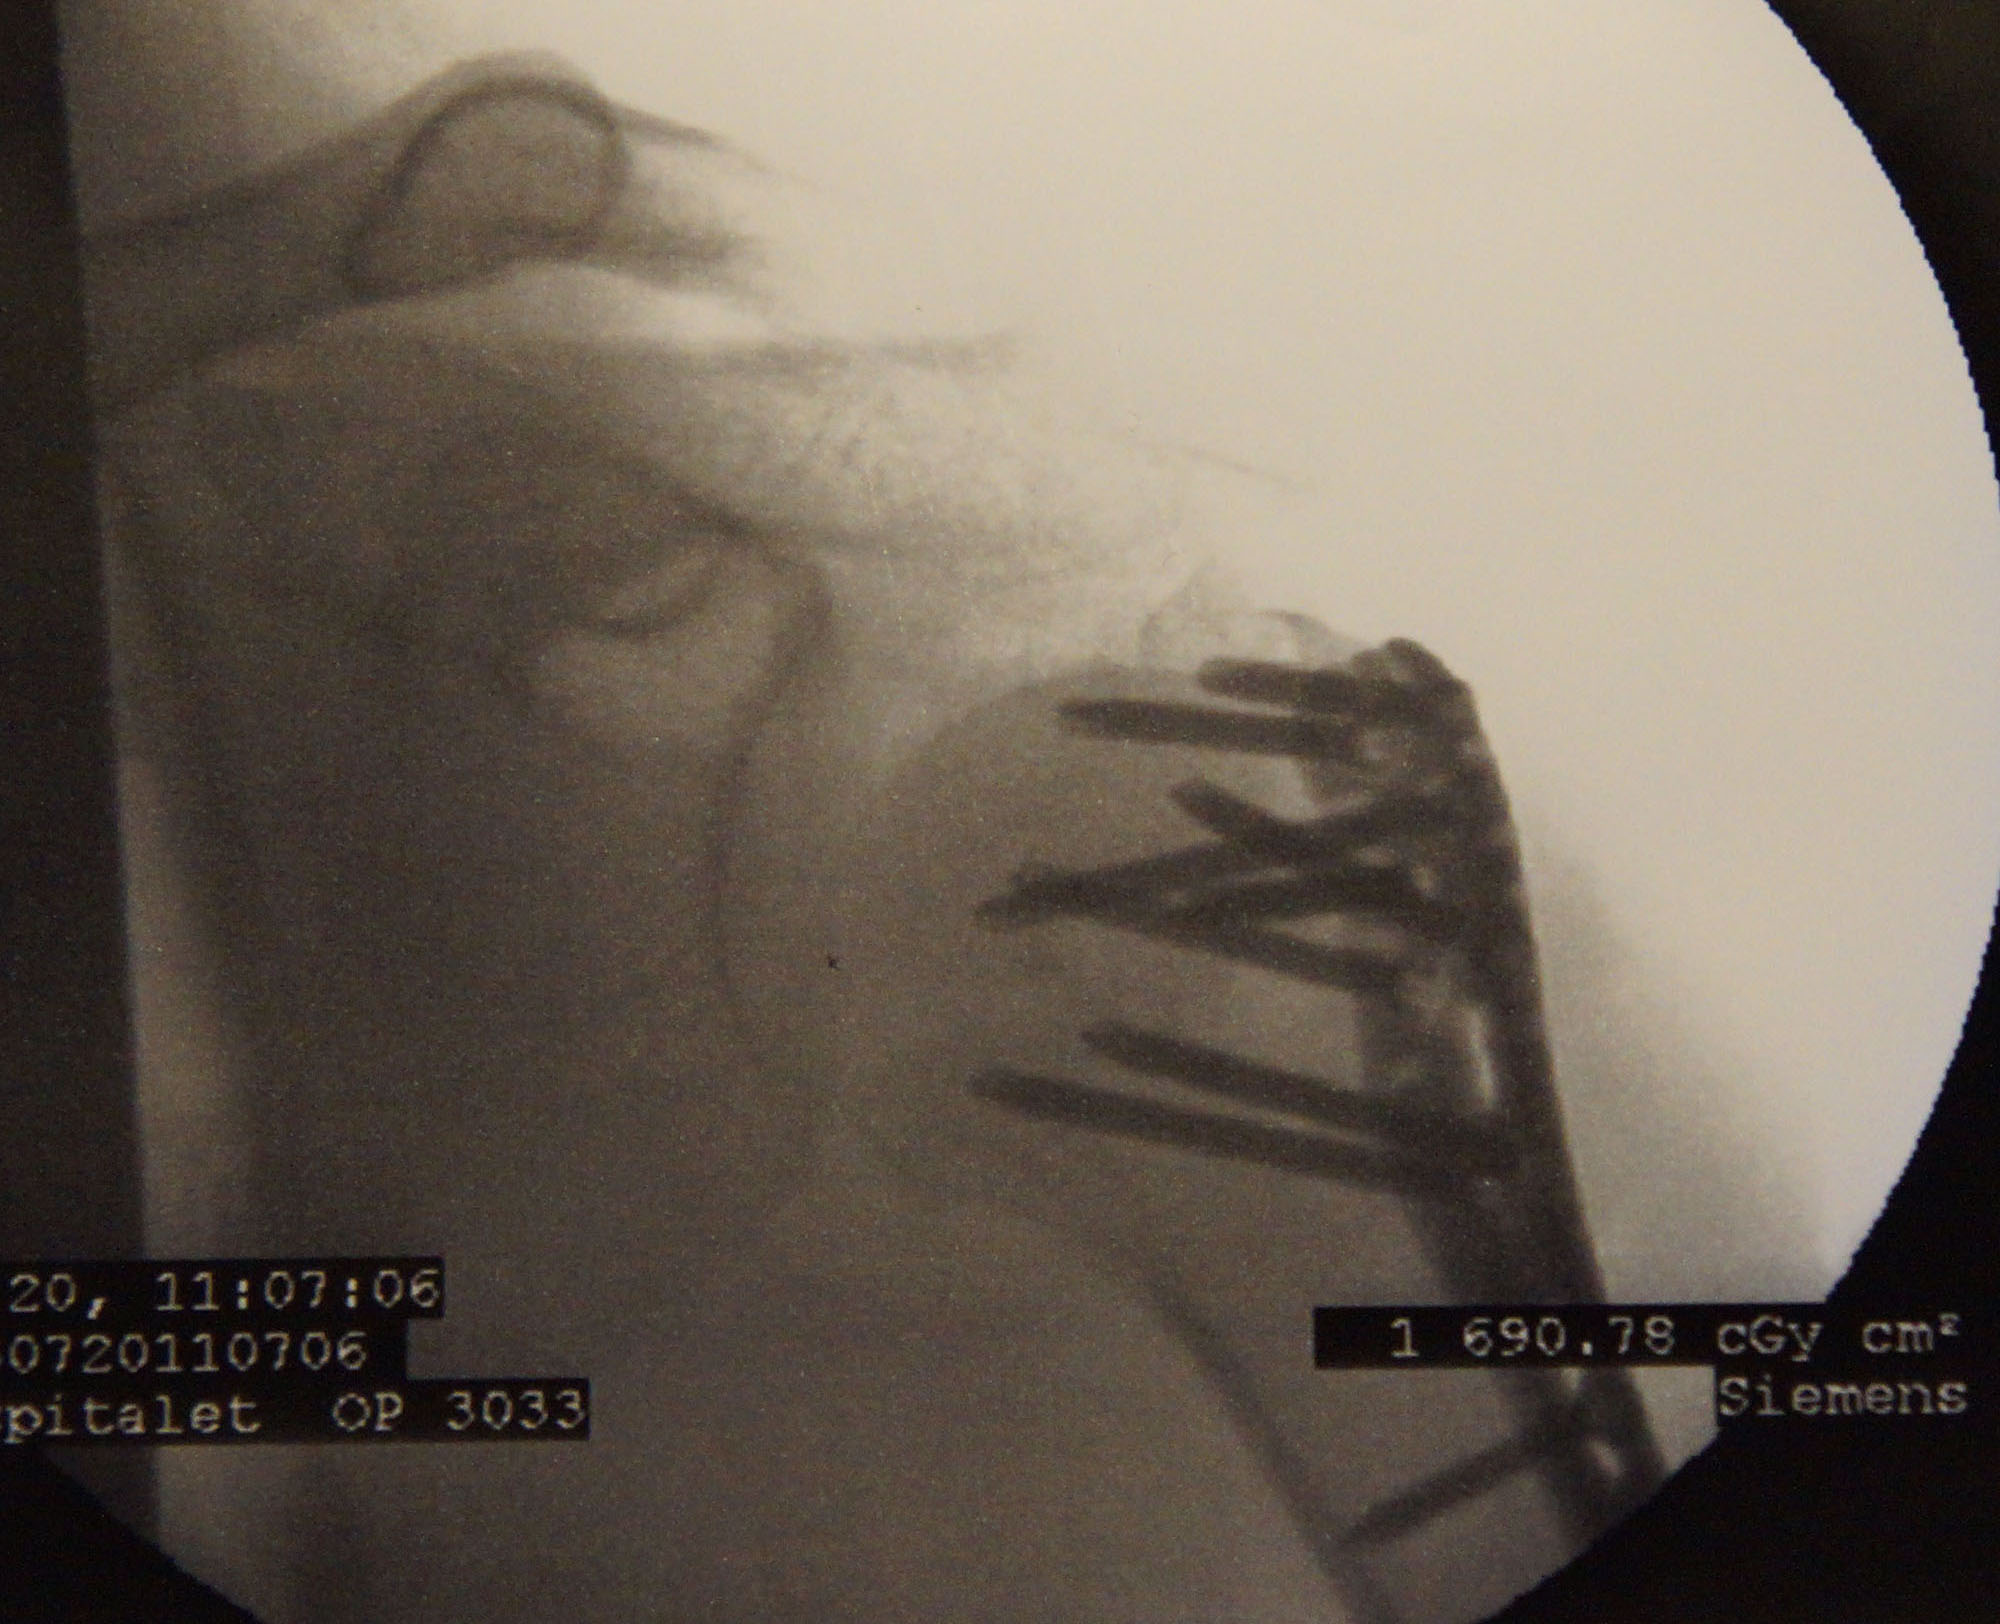

Det var mere end et år side jeg var på bane. Min venstre skulder er næsten 50% brugbar. Kan løfte den næsten op til vandret. Nå, næsten, hvis jeg vrider overkroppen. :-) Så, nok ingen problem når jeg drejer til venstre, men nok lidt problem når jeg drejer til højre. Det skal prøves.